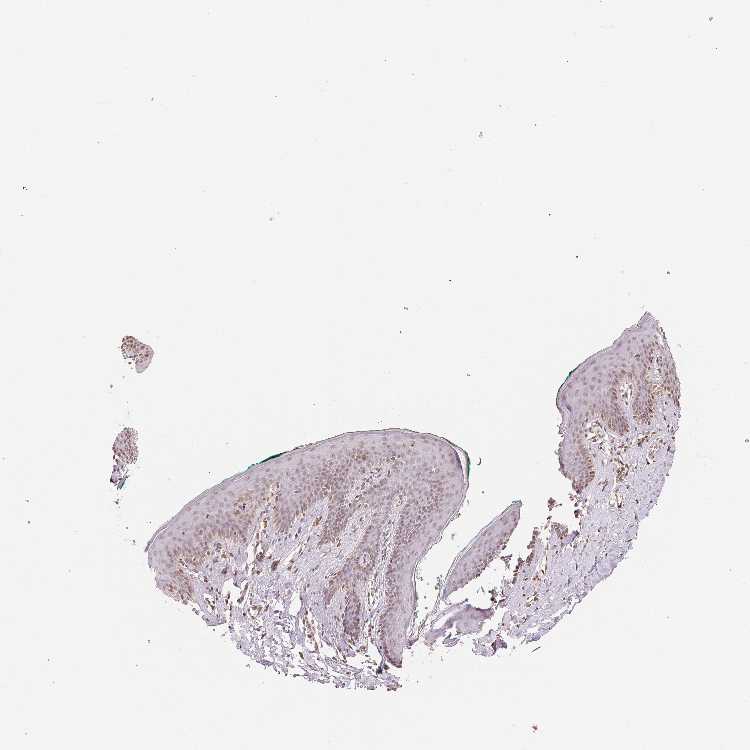

SKIN 2 - Antibody stainingi

Antibody staining in the annotated cell types in the current human tissue is reported as not detected, low, medium, or high, based on conventional immunohistochemistry profiling in selected tissues. This score is based on the combination of the staining intensity and fraction of stained cells.

Each image is clickable and will lead to virtual microscopy that enables deeper exploration of all samples and also displays staining intensity scores, fraction scores and subcellular localization as well as patient and tissue information for each sample.

Antibody HPA049805

Epidermal cells Low